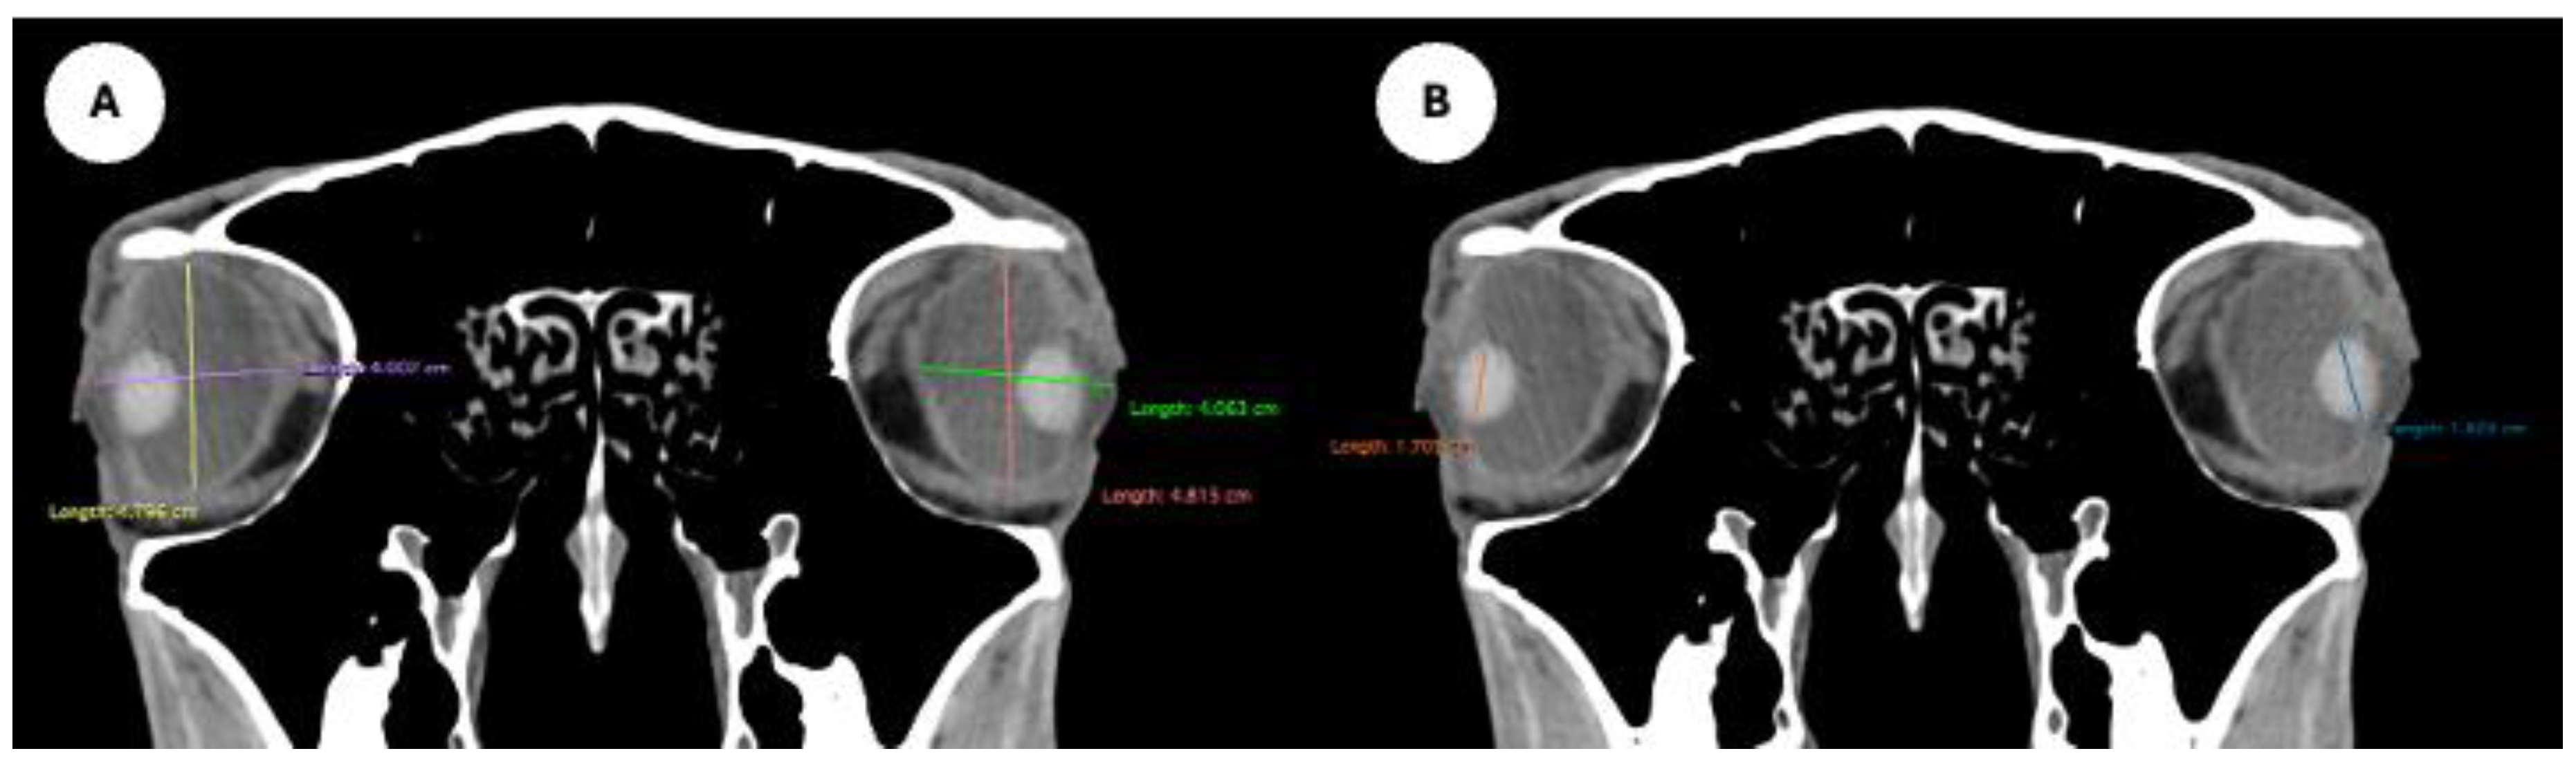

- Orbital cavity height: Maximal dorsoventral distance of the orbital cavity at the level of the eyeball.

- Orbital cavity rostrocaudal length: Maximal anteroposterior distance of the orbital cavity measured at the level of the eyeball.